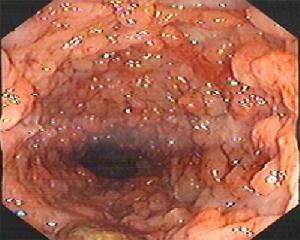

3.結腸鏡檢查,結腸鏡檢查是診斷潰瘍性結腸炎最重要的手段之一,既可直接觀察結腸黏膜的變化,可確定病變的基本特徵和範圍,又能進行活組織檢查,因此,可以大大提高診斷潰瘍性結腸炎的準確率,對本病的診斷有重要價值。此外,在潰瘍性結腸炎癌變監測過程中也起著十分重要作用。但病變嚴重並疑將穿孔、中毒性結腸擴張、腹膜炎或伴有其他急腹症時,應列為結腸鏡檢查的禁忌證。內鏡下黏膜形態改變主要表現為糜爛、潰瘍和假息肉形成,表現為:黏膜多發性淺表潰瘍,伴充血、水腫,病變多從直腸開始,呈瀰漫性分布;黏膜粗糙呈細顆粒狀,黏膜血管模糊,質脆易出血;病變反覆發作者可見到假息肉,結腸袋消失、腸壁增厚等表現。

(1)在活動期,受累的同一腸段的改變幾乎均勻一致。初期主要是黏膜充血、水腫,血管紋理紊亂、模糊,半月襞增厚,腸管常呈痙攣狀態;隨後黏膜面變粗糙,出現瀰漫分布、大小較一致的細顆粒,組織變脆,有自然出血或接觸出血,腔內有黏液性分泌物;進一步發展則黏膜出現糜爛,伴有許多散在分布的黃色小斑,乃隱窩膿腫形成後膿性分泌物附於腺管開口所致;而後黏膜面形成許多潰瘍,潰瘍較小而表淺,針頭樣、線形或斑片狀,形態不規則,排列無規律,圍繞腸管縱軸和橫軸相互交錯,這是潰瘍性結腸炎內鏡下的重要特徵。周圍黏膜亦有明顯充血糜爛等炎性反應,幾乎無正常殘存黏膜可見。

(2)在緩解期,內鏡的主要表現為黏膜萎縮和炎症性假息肉。因本病的病理改變一般不超過黏膜下層,所以不形成纖維化和瘢痕,可完全恢復正常。病情較輕者,炎症消退後腸黏膜充血、水腫也逐漸消失,潰瘍縮小呈細線狀或癒合消失,滲出物吸收;慢性持續型或復發緩解型病例,腸黏膜出現萎縮性改變,色澤變得蒼白,血管紋理紊亂,黏膜正常光澤喪失,略顯乾燥,殘存黏膜小島可因上皮和少量纖維組織增生可形成假性息肉,假性息肉多少不定,大小不等,可有蒂或無蒂。黏膜橋是潰瘍反覆發作向下掘進,而邊緣上皮不斷增生,在潰瘍上相對癒合連線,兩端與黏膜面連線而中間懸空的橋狀形態而形成的,並非潰瘍性結腸炎所特有。

(3)在晚期,嚴重且反覆發作的潰瘍性結腸炎者,可出現結腸袋消失,腸管縮短,腸腔狹窄,黏膜面粗糙呈蟲咬樣,形成X線上所謂鉛管樣結腸。

Ⅱ級:黏膜充血、水腫,呈顆粒狀,黏膜脆性增加,接觸易出血或散在自發性出血點。

Ⅲ級:黏膜明顯充血、水腫、粗糙,明顯自發性出血和接觸性出血。有較多炎性分泌物,多發性糜爛與潰瘍形成。